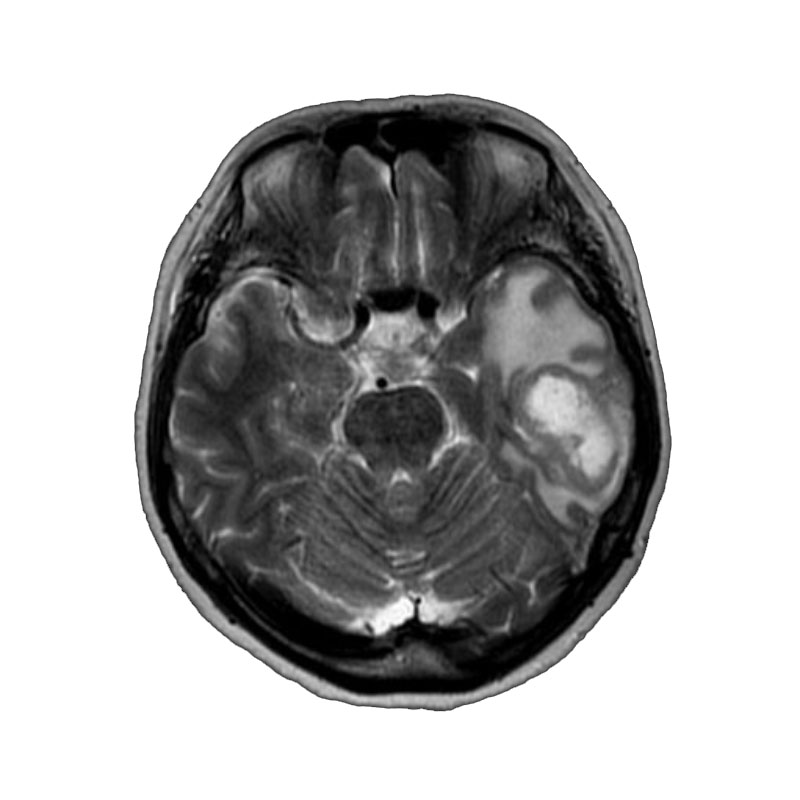

右側頭葉脳腫瘍

摘出術

南田/野本/佐伯